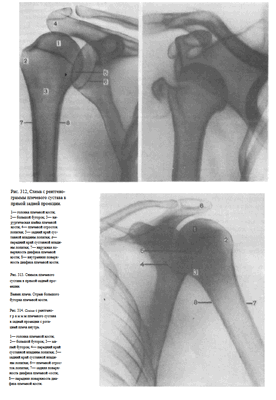

На снимках плечевого сустава хорошо видны головка плечевой кости, суставная впадина лопатки, плечевой отросток лопатки.

На рентгенограмме, произведенной в условиях супинации кисти, хорошо виден большой бугорок плечевой кости, который здесь является краеобразующим (рис.312, 313). На снимках, произведенных в условиях пронации кисти, большой бугорок виден хуже, но по медиальному контуру над хирургической шейкой становится виден малый бугорок (рис.314). Медиальный и латеральный контуры тела плечевой кости при этих двух вариантах укладки на снимках образованы разными ее поверхностями. На снимке при супинации кисти медиальный контур образован внутренней, а латеральный — наружной поверхностью тела плечевой кости; на снимке при пронации кисти медиальный контур отображает переднюю, а латеральный — заднюю поверхность тела плечевой кости.

Наиболее информативными для оценки плечевого сустава являются снимки, выполненные в условиях разгибания верхней конечности и супинации кисти. Снимки в задней проекции с ротацией плеча внутрь являются дополнительными или же выполняются в тех случаях, когда снимок в прямой задней проекции с разгибанием руки произвести не удается.

Информативности снимка. На снимке видны головка плечевой кости, края суставной впадины лопатки, плечевой и клювовидный отростки.

Краеобразующими являются малый бугорок плечевой кости, передняя поверхность диафиза плеча по верхнему контуру и задняя поверхность диафиза плеча по нижнему контуру (рис.318, 319).